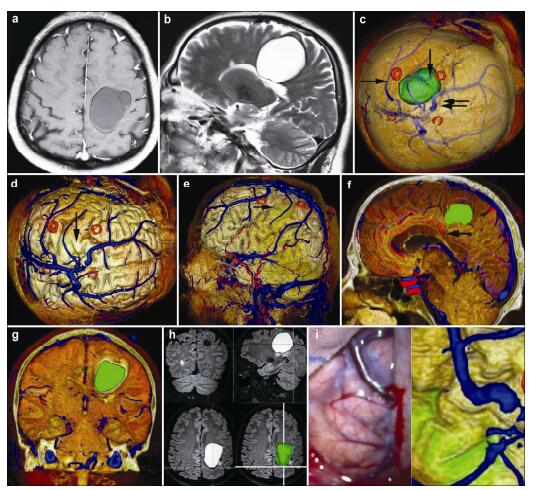

20170308100832  Figure 6 Magnetic resonance imaging, reconstruction images, surgical incision, 3D view, and actual operative view in a 55-year-old male patient with a meningioma in right frontal lobe. (a, b) T1 enhancement scans: The tumor presented as homogenous enhancement. (c) 3D reconstruction (skull semitransparent): The tumor (vertical single arrow) located behind the coronary suture (horizontal double arrow) and adjacent to sagittal suture. The right central sulcus vein (horizontal single arrow) is under the tumor. (d) 3D reconstruction (do not show the skull): The tumor is adjacent to the superior sagittal sinus (vertical single arrow) and superior sagittal sinus (vertical single arrow). (e) 3D reconstruction (lateral view): The tumor is adjacent to the superior sagittal sinus and locates on the surface of the brain above the right central sulcus vein (horizontal single arrow). The markers are around the tumor. (f) Intraoperative situation: The intraoperative situation is consistent with 3D reconstruction images. (g) Surgical incision. (h) 3D view: The images of 3D reconstruction are consistent with that of T1 enhancement MRI.